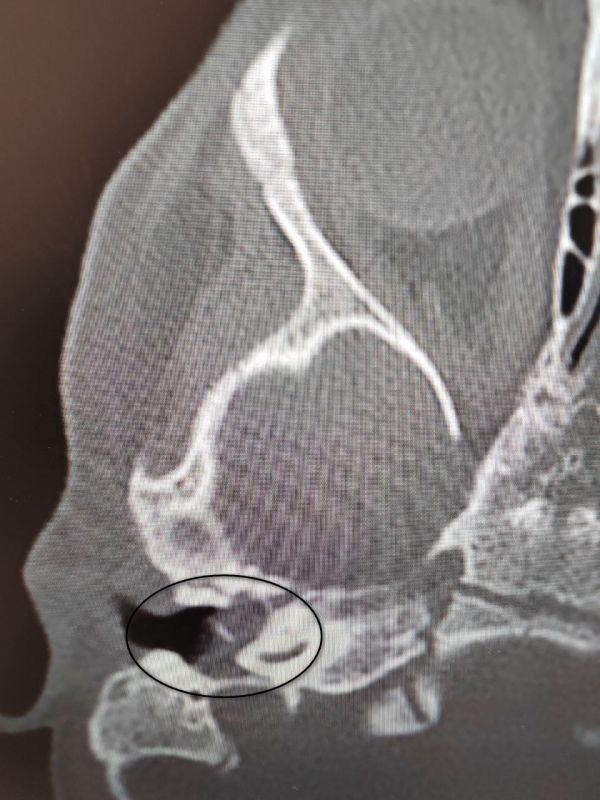

Малышка поступила в ВОДКБ №1 с правосторонним хроническим гнойным средним отитом и подозрением на врождённую холестеатому барабанной полости (кистозное патологическое образование в среднем ухе). Ей грозила потеря слуха.«Всё...

У ребенка был правосторонний хронический гнойный средний отит и подозрение на врожденную холестеатому барабанной полости (кистозное патологическое образование в среднем ухе). Это заболевание встречается особенно редко в таком...